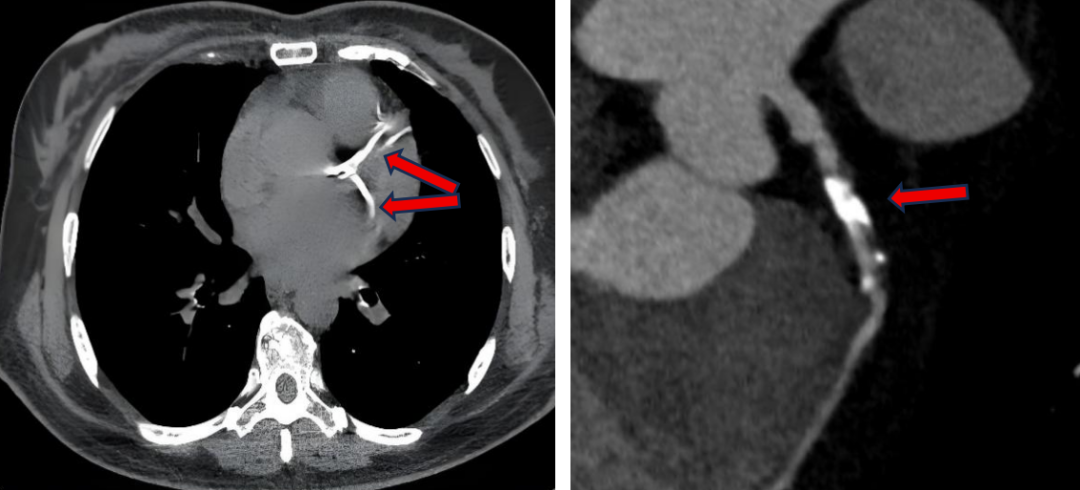

注:胸部CT及冠状动脉CTA上表现,红色箭头指向发亮发白部分为钙化